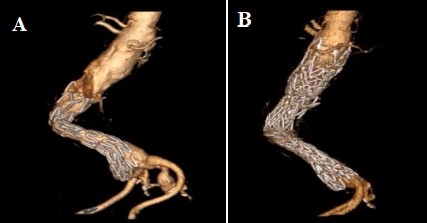

Hybrid utilization of endografts prevents endoleaks and migration when shorter thoracic endografts are utilized. Also, reintervention with Funnel-EVAR is a potential alternative solution for migrated EVAR (Fig. 5A,B).

Fig. 5.Treatment of migrated endograft with Funnel EVAR. Preoperative CTA of a migrated index EVAR procedure (A) and postoperative 6th month CTA control with no complication (B). EVAR, endovascular aneurysm repair; CTA, computed tomographic angiography.